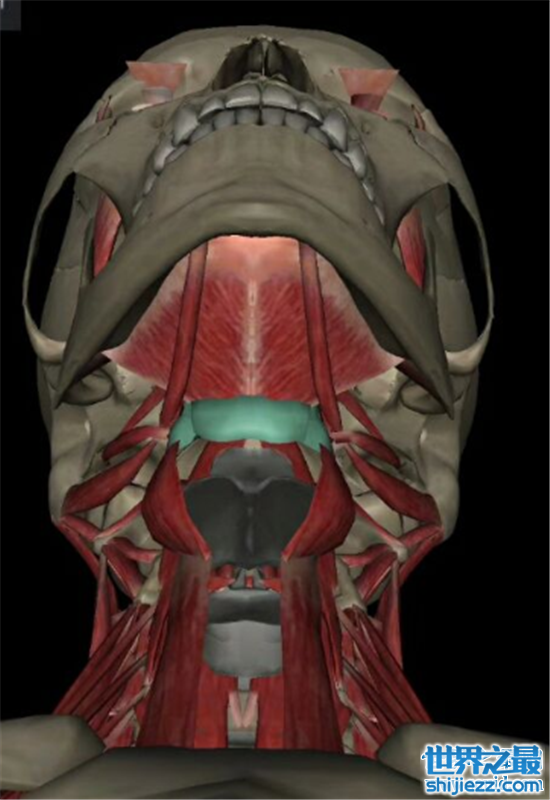

8、舌骨

舌骨相较于人身体中的其它骨骼来说,是非常不显眼的,它本身也并不跟其它骨骼相连接。但是舌骨对于人的发声有着超乎寻常的意义,不依靠舌骨,人类很难进行口腔的多重共鸣,这也算得上是关于人体骨骼的十大事实中最冷的一个知识了。